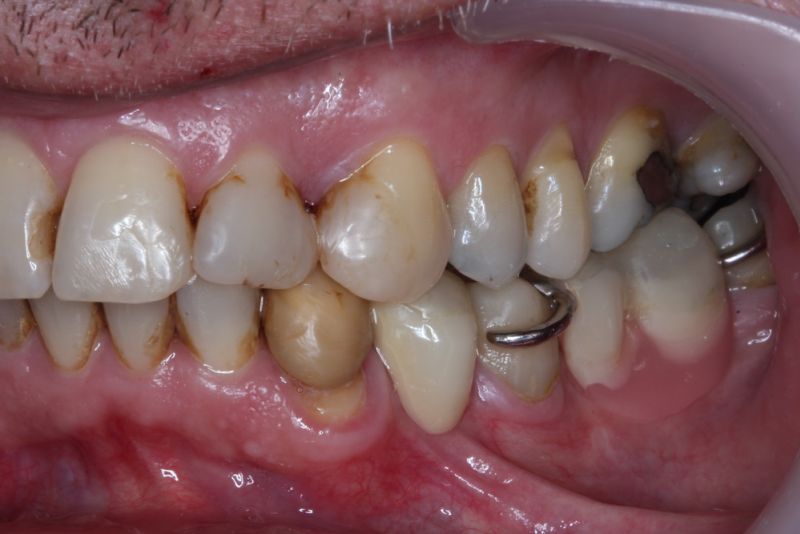

Der Patient hat in den Jahren 2012-2014 eine kieferorthopädische Erwachsenenbehandlung durchführen lassen.

Nach Meinung des Patienten wurden im linen Unterkiefer mehrere Zähne, die vermeintlich schmerzten, nach der Entfernung bestanden die Beschwerden aber weiter.

Erkennbar ist die massive Abweichung der habituellen Bisslage von der neuromuskulär zentrierten Bisslage.